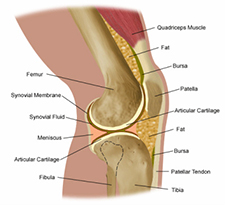

What Are Joints?

Joints are two bones joined together in a socket that allows movement. The joint is composed of bones, cartilage, tissue, muscle and fluid. The ends of the bones are covered by cartilage, which keeps the bones from rubbing together. Cartilage acts like a shock absorber to the bones. Tissue helps make up the inner wall of the socket and creates a seal to hold in the fluid. The fluid provides nutrients and lubrication to the inner wall and cartilage.

Joints are grouped according to motion types; gliding, hinge, ball and socket, and pivoting. Because of the sensitive location of joints, the pressure exerted on them and their continuous use, they are prone to pain and swelling.